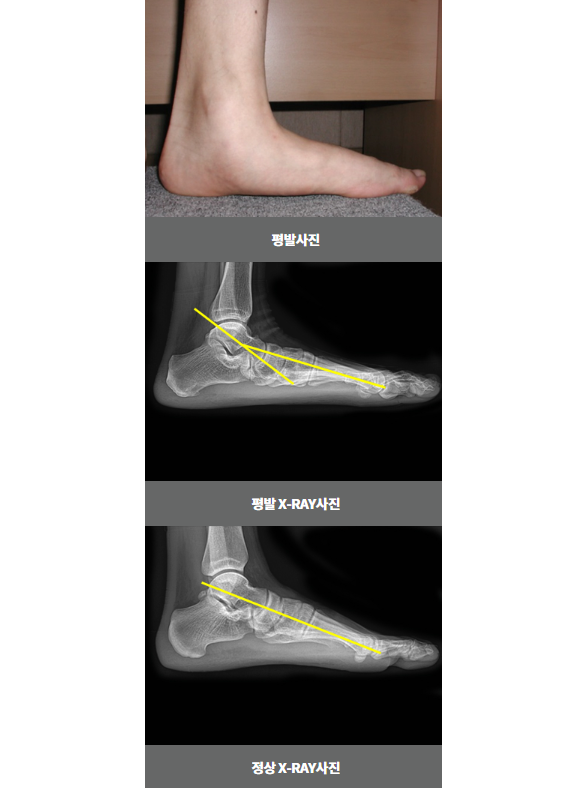

평발

평발은 보행 시 아치가 무너지면서 뼈의 정렬이 변화되어 안쪽으로 틀어지는 질환으로

평발인 경우 발의 피로도가 증가하며 신체의 균형이 무너질 수 있어, 초기의 진단 및 지속적인 관리가 필요합니다.

비수술 치료 : 약물, 고정 (깁스 또는 보조기), 물리치료, 주사치료, 도수치료